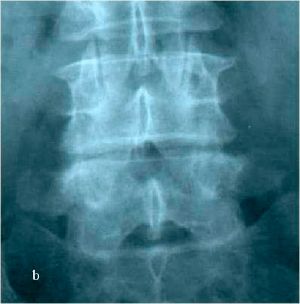

При МРТ и рентгенографии поясничного отдела позвоночника выявляется спондилолизный антеролистез L4 позвонка со стенозированием позвоночного канала на указанном уровне, грыжа мп диска L4-L5 слева. (Рис.7а,б. Рис.8а,б)

| Рис. 8а,b. Рентгенограмма поясничного отдела позвоночника в боковой (а) и прямой (b) проекциях до операции. Стрелкой показано смещение тела L4 позвонка кпереди. |